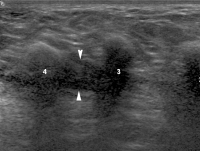

Abbildung 1a-b: Sonographischer Transversalschnitt (a) und Plastinationsschnitt (b) durch ein anatomisches Handgelenkspräparat mit Darstellung des Nervus medianus. In der Korrelation zeigt sich der Aufbau des Nervs aus mehreren Faszikelgruppen (Pfeile), welche durch echoreiches epineurales Gewebe voneinander getrennt und durch eine äußeres Epineurium (Pfeilspitzen) gegen die Umgebung abgegrenzt sind. FS: Flexorensehnen, PQM: Pronator quadratus-Muskel.